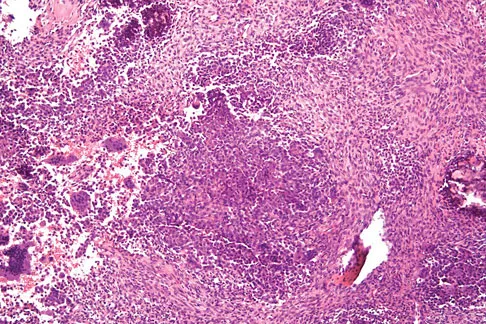

A 54-year-old woman reports worsening pain in her buttock, especially when sitting for long periods of time. She has occasional pain and paresthesias radiating down her posterior leg. She has no significant medical history. MRI scans are shown in Figures 15a and 15b and a biopsy specimen is shown in Figure 15c. What is the most likely diagnosis?

Explanation

The biopsy specimen shows a wavy collagenous matrix with elongated cells; this is most consistent with neurofibroma. The patient has a mass in the region of the sciatic nerve. Imaging characteristics, homogeneous and very low signal on T1-weighted and very high signal on the T2-weighted sequences, are consistent with a myxoid-type lesion. These include myxoma, myxoid sarcomas, and nerve sheath tumors. Campanacci M: Bone and Soft Tissue Tumors, ed 2. New York, NY, Springer-Verlag, 1999, pp 1135-1136